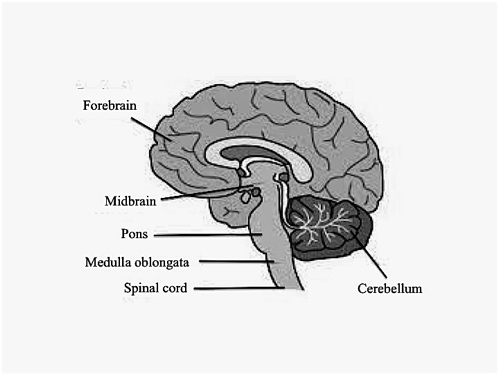

Medulla Oblongata: What It Is, Function & Anatomy

The Anatomy of the Medulla Oblongata

The Medulla Oblongata - Internal Structure - Vasculature

Medulla Oblongata Location, Function, and Features

Medulla oblongata – Lancaster Glossary of Child Development

Medulla Oblongata

Medulla Oblongata - The Definitive Guide | Biology Dictionary

The Medulla Oblongata and Pons

Medulla - The Brain and Psychology

Medulla Oblongata: Definition, Structure And Functions